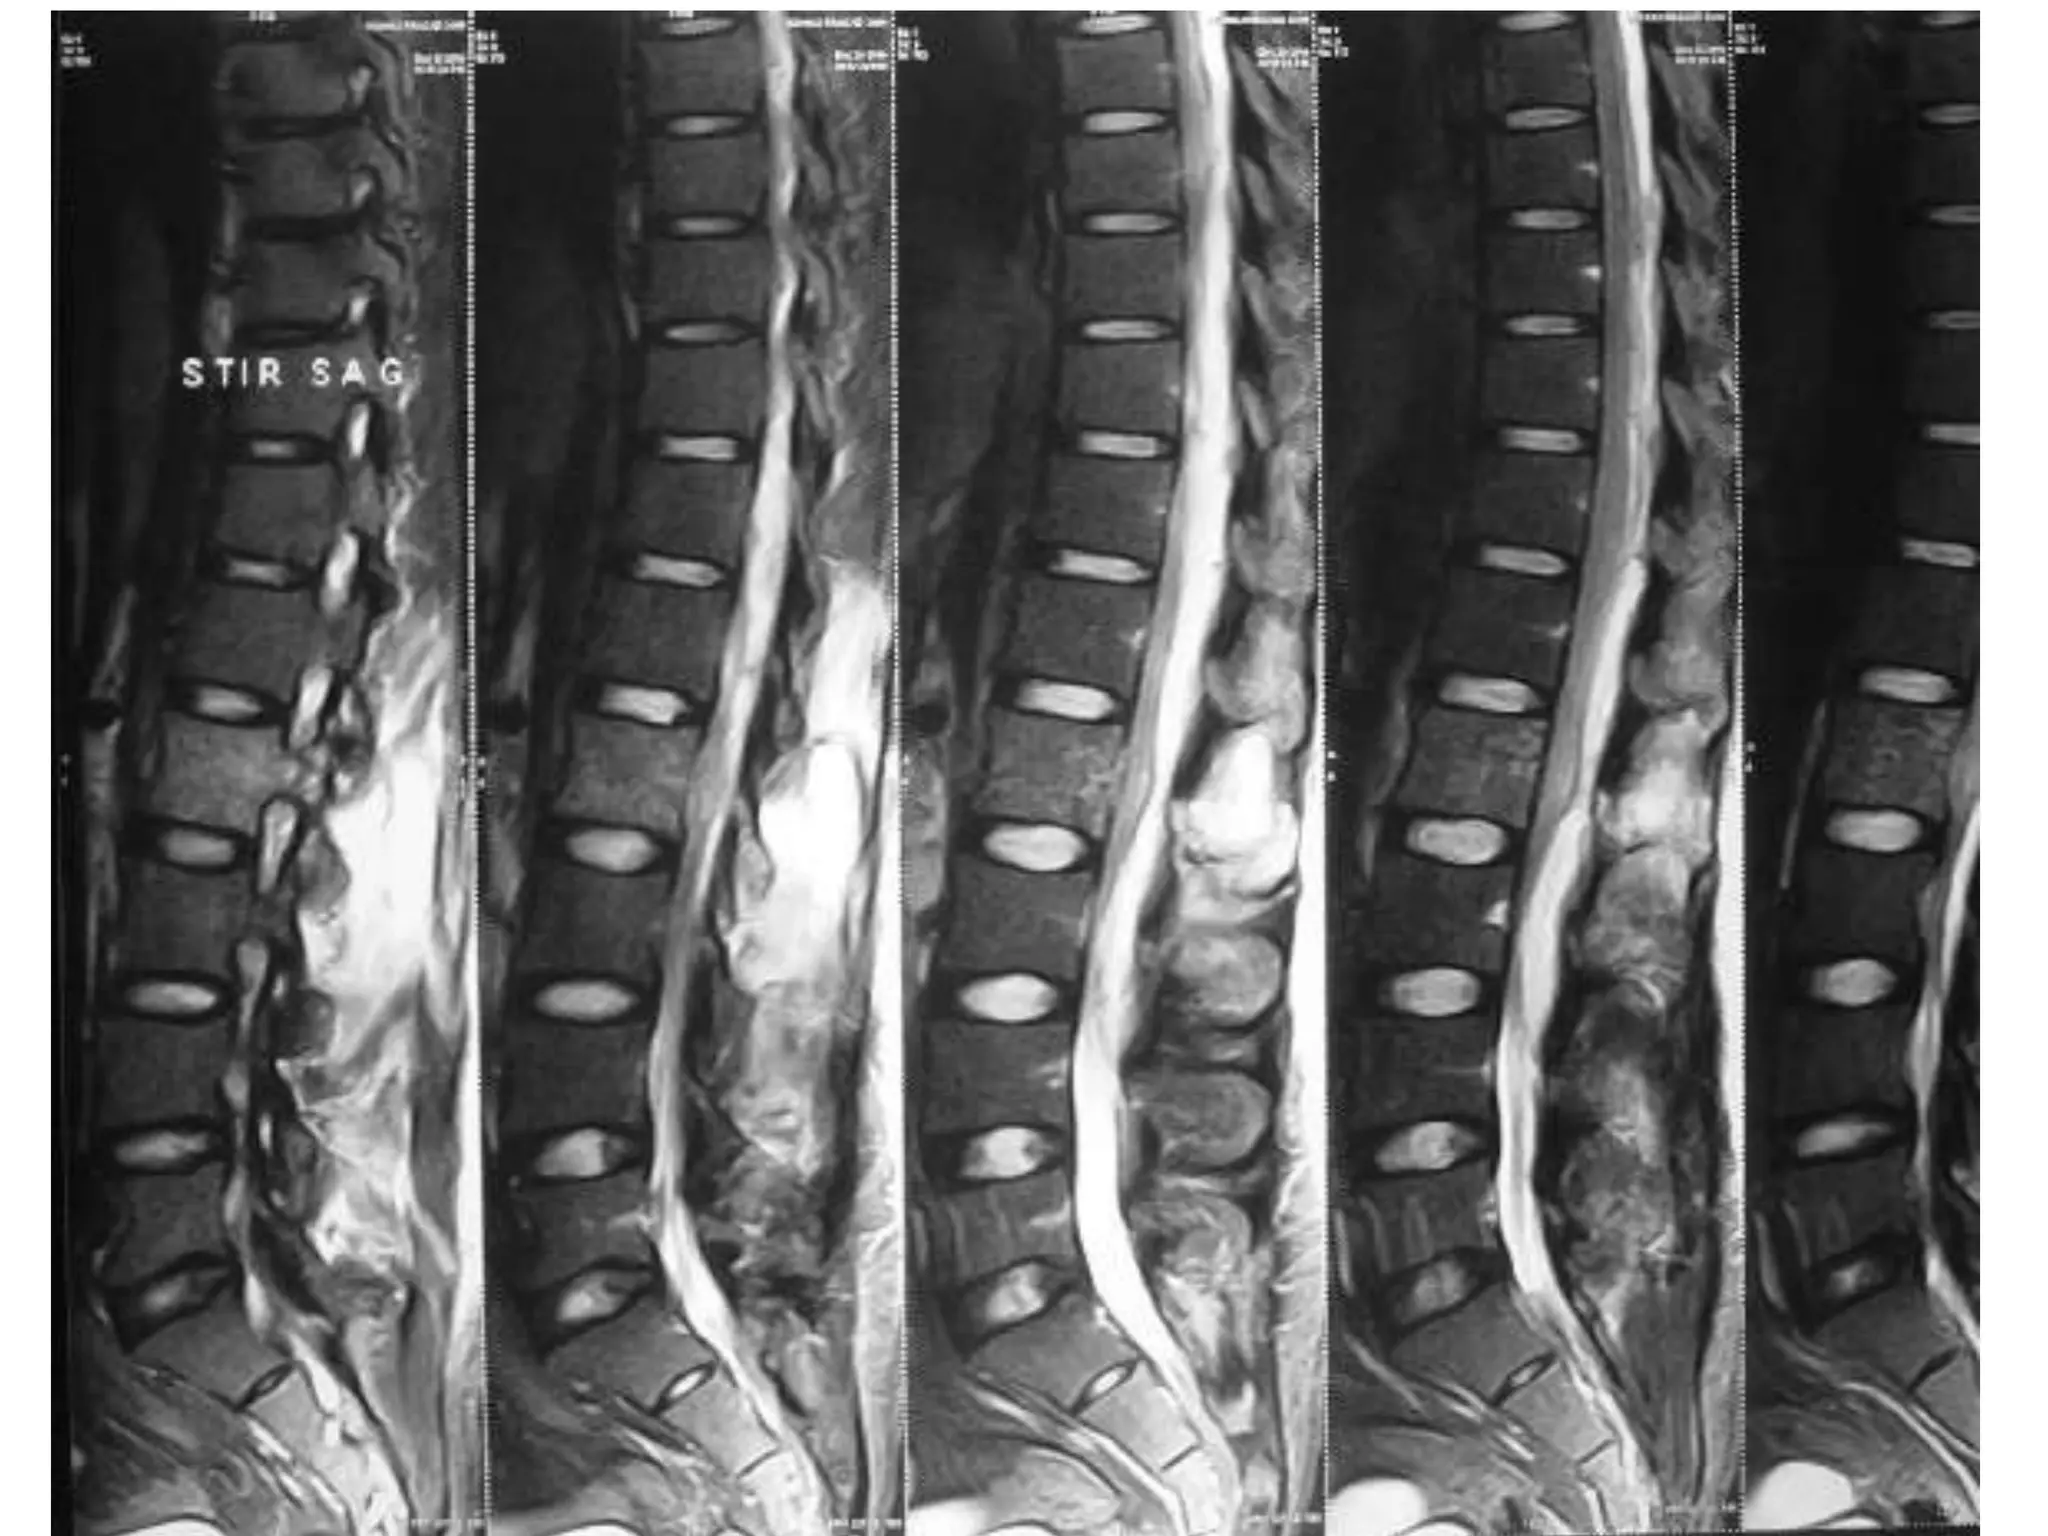

AV malformation